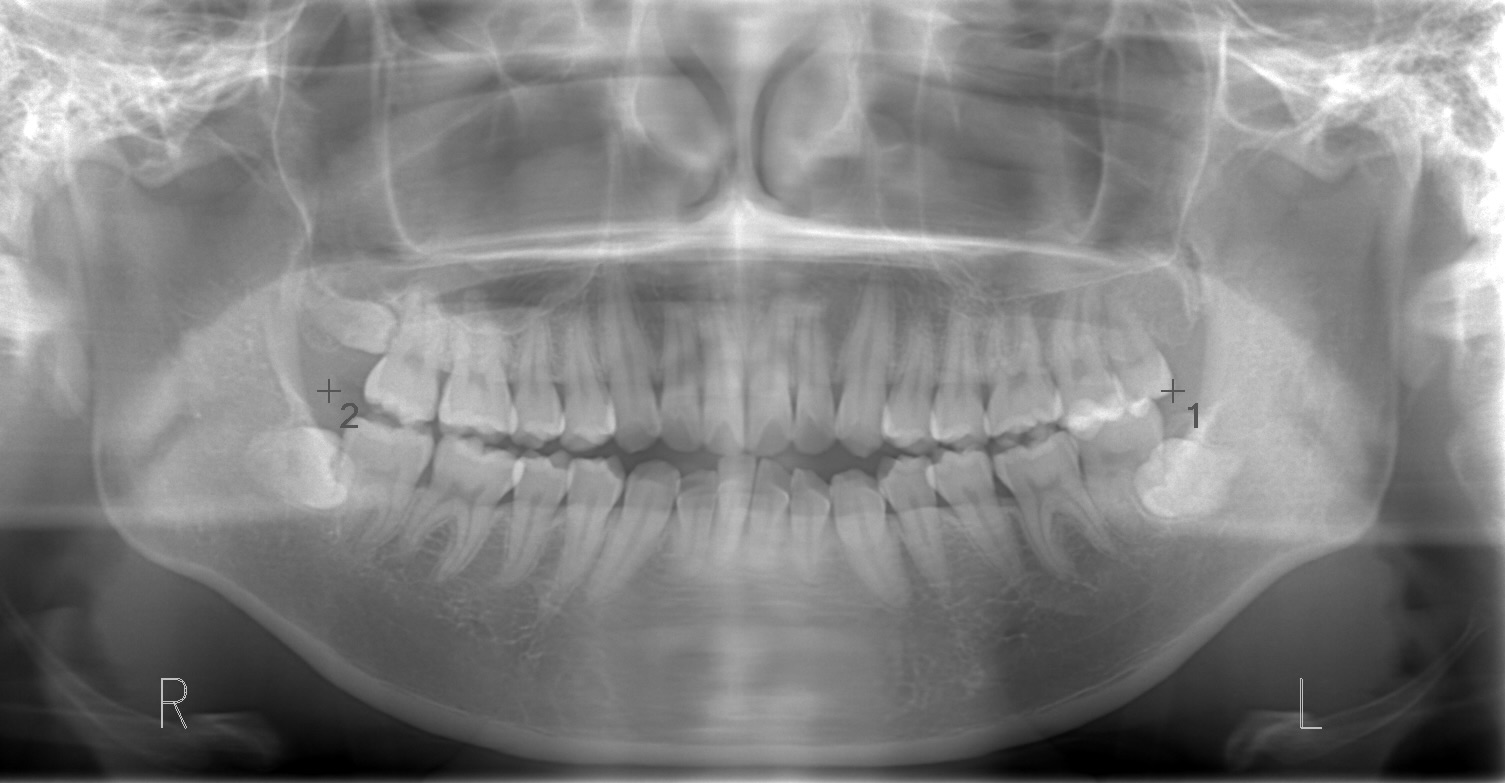

下顎臼歯部を遠心に動かしたいが、埋伏智歯があるため動かせない。また小臼歯抜歯によりスペースを確保できたとしても開口であるため下顎の歯は並んでも上顎前歯部に下顎前歯部が届かなくなる可能性が高い。

下顎左側第2大臼歯が虫歯になっていたこと、また前歯を並べるためには臼歯部の遠心移動が必要であることを考慮し、第2大臼歯を抜歯して埋伏している親知らずを咬合参加させるように矯正治療で動かしていく。